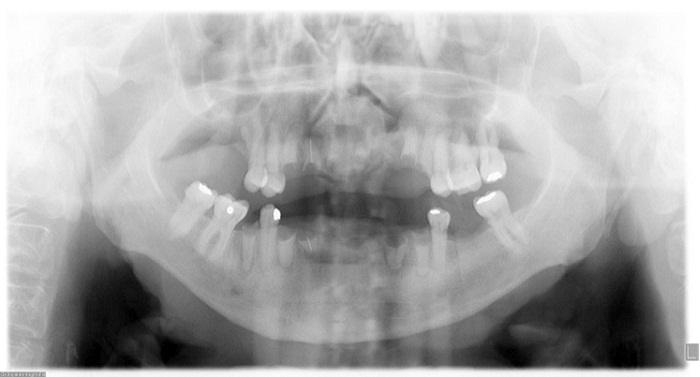

No se encontraron lesiones en el examen intraoral. La paciente era edéntula parcial con desarmonía oclusal sin previo tratamiento de rehabilitación (figura 4). Radiográficamente, se encontraron múltiples espacios edéntulos, múltiples restos radiculares en la zona anterior de los maxilares superior e inferior, calcificación del ligamento estilohioideo y ausencia de queratoquistes mandibulares que pudieran asociarse con el síndrome de Gorlin-Goltz (figura 5).

El síndrome de Gorlin-Goltz, también llamado síndrome del nevoide de células basales, se caracteriza por presentar anomalías del desarrollo que se manifiestan clínicamente con la presencia de numerosos CBC micro- y macroscópicos, hamartomas benignos del folículo piloso, queratoquistes odontogénicos mandibulares, hiperqueratosis palmoplantar, anomalías esqueléticas (costillas bífidas, sindactilia), características craneofaciales específicas (cráneo agrandado, hipertelorismo y prominencia frontal), calcificaciones intracraneales ectópicas y dismorfia facial con macrocefalia, fisura labiopalatina y anomalías oculares graves (1,4). En 2007, Moctezuma y colaboradores (19) indicaron los criterios para el diagnóstico del síndrome de Gorlin. Según estos autores, se requiere que el paciente cumpla con dos criterios mayores y un criterio menor o un criterio mayor y dos criterios menores (20,21). El diagnóstico de síndrome nevoide de células basales de la paciente de este artículo se confirmó con exámenes complementarios: radiografías de tórax y simple de cráneo (figuras 9 y 10).

* Partes blandas normales, estructuras óseas conservadas, corazón de tamaño normal, cayado aórtico de calibre normal, ausencia de adenopatías.

* Suturas craneales normales, surcos vasculares normales, arcos cigomáticos y silla turca normal, calcificaciones fisiológicas de la hoz cerebral.

Después del seguimiento multidisciplinario que se dio a la paciente, se pudo identificar la presencia de criterios mayores (presencia de dos o más CBC, piqueteado palmoplantar) y menores (calcificación laminar de la hoz del cerebro, antecedente de fibromas ováricos) que permitieron establecer el diagnóstico de síndrome de Gorlin-Goltz o síndrome nevoide de células basales y remitir a la paciente a las especialidades médicas en la institución de salud pertinente (Instituto Nacional de Cancerología) para poderle brindar un tratamiento integral.